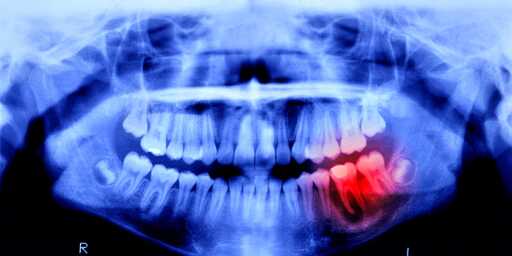

Now, scientists will see just how similar, because humans are undergoing a similar trial. Lasting 11 months, this study focuses on 30 males between the ages of 30 and 64—each missing at least one tooth. The drug will be administered intravenously to prove its effectiveness and safety, and luckily, no side effects have been reported in previous animal studies.